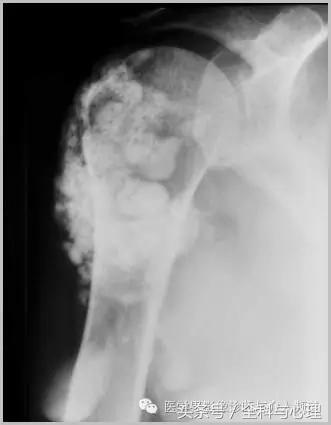

五、滑膜软骨瘤病

1°少见,病灶数量多,大小均匀,相邻关节正常。

2°多见,病灶数量少,大小不一,多伴有退行性骨关节病。

滑膜骨软骨瘤病 1°

滑膜骨软骨瘤病 2°

滑膜骨软骨瘤病